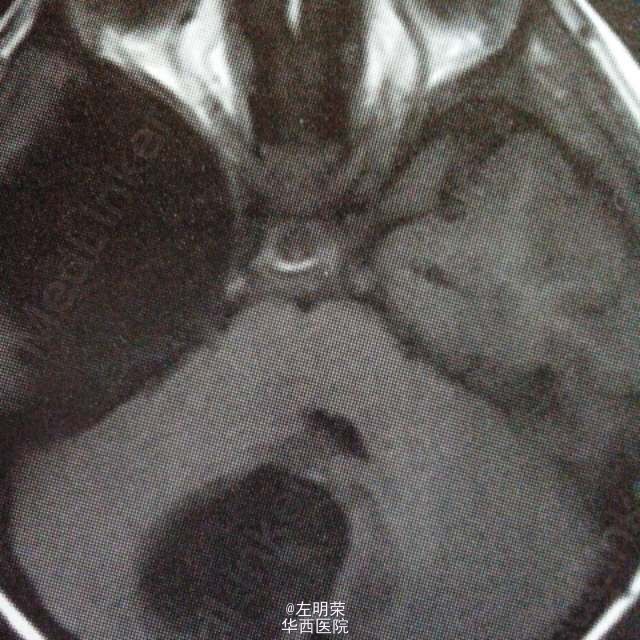

6岁小儿,主诉间断性头痛伴恶心,呕吐6天。影像特点:右侧小脑半球可见明显强化的囊实性占位,囊内可见出血后形成的液平,瘤旁轻微水肿。考虑星形细胞瘤,髓母细胞瘤,室管膜瘤可能。行手术切除治疗,见囊实性肿块,囊内坏死出血,肿瘤血供丰富,边界不清,近全切。病理结果:髓母细胞瘤